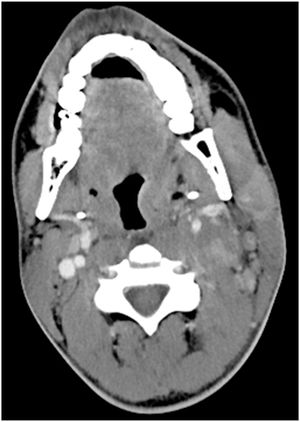

Image IQ: 20-year-old Male, Left Neck Pain

20-year-old male with no medical history presents with left-sided neck pain for 5 days.